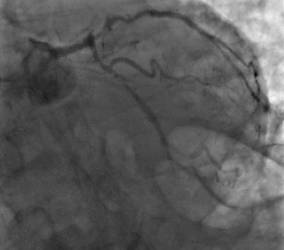

Se trata de un procedimiento que elimina las obstrucciones existentes en las arterias coronarias. Los doctores Juan Vicente Herrero Vilar y Eva Rumiz González, especialistas de la Unidad de Hemodinamia y Cardiología Intervencionista del Hospital Quirónsalud Valencia

, nos detallan esta técnica: "El dispositivo llamado Rotablator está basado en una pequeña fresa u oliva impregnada en partículas de diamante que tiene una rotación de 160.000 revoluciones por minuto y es capaz de pulverizar la obstrucción respetando las estructuras normales de la arteria. Sin esta técnica es imposible en muchos casos el implante de un stent, ya que al tratarse de obstrucciones con alto contenido de calcio impiden su avance dentro de la propia arteria".

Para poder entender su utilidad debemos tener en cuenta que una de las mayores dificultades a las que se enfrentan los especialistas a la hora de colocar un stent reparador de una lesión coronaria son las zonas calcificadas, que dificultan la entrada del propio stent en la arteria. Partimos del hecho de que el 95% de los pacientes con obstrucciones arteriales son tratados mediante angioplastia coronaria e implante de stent. Sin embargo, entre ellos, se dan casos con un grado de calcificación de las obstrucciones tan alto que el acceso se hace realmente complicado. Y es precisamente en estas ocasiones cuando la aterectomía rotacional se hace más útil, e incluso necesaria, ya que el Rotablator pulveriza las placas calcificadas, dejando intactas el resto de zonas de la pared artificial, y dejando el camino libre para el paso del stent.